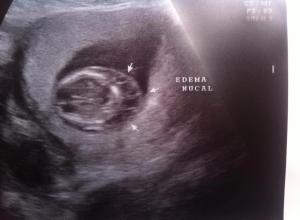

Como teníamos ya un antecedente, gracias a unos clientes (ahora amigos), fuimos con un especialista, esto con la finalidad de saber que todo fuera bien con nuestro bebe, lamentablemente las cosas no estaban tan bien, aunque era muy pequeño el doctor detecto un pequeño problema cerca de su craneo, el cual no había aun la seguridad de saber que pudiera ser. Habia que mandar a hacer algunos análisis, y esperar a que creciera un poco mas, y ver los resultados.

El dia de ayer, tuvimos otra revisión, después de un ultrasonido, nos dieron la noticia el bebe tiene alguno de los 3 síndromes que mencionaremos, Síndrome de Edwards, Síndrome de Patau, o Síndrome Down, aparte de eso, tiene una pequeña complicación en su corazón, algo en su “Ductus Venoso, con onda “A” reversa”, (Cada latido que da su corazon, la sangre que corre por sus venas, tiene un pequeño regreso).